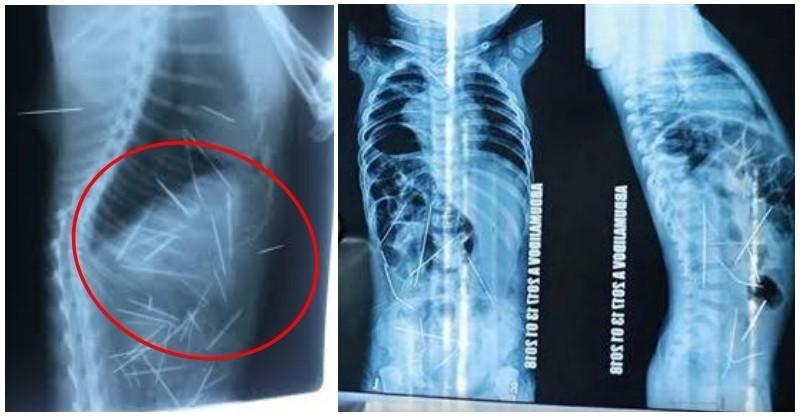

一位11個月大的男嬰因為高燒不退,加上排尿不順,母親便急忙帶著他到醫院求診,醫生原以為是是感染肺炎,但在經過X光檢查後,卻意外發現男嬰體內有16根金屬製長針,畫麵讓人看了頭皮發麻。

長針散布在男嬰的體內各處,包括心臟、脖子、膀胱和脊椎等部位,都能看到長針的蹤影。

醫生也緊急開刀處理,經過9個小時的手術後,順利將他體內的10根針移除,其中有9根是在腹部,另一根則是在脖子。

另外也請來心臟外科醫師,幫忙將靠近心臟處的3根長針也取出,目前男嬰體內還有3根針,近日也將再度接受手術將剩下的針給取出來。